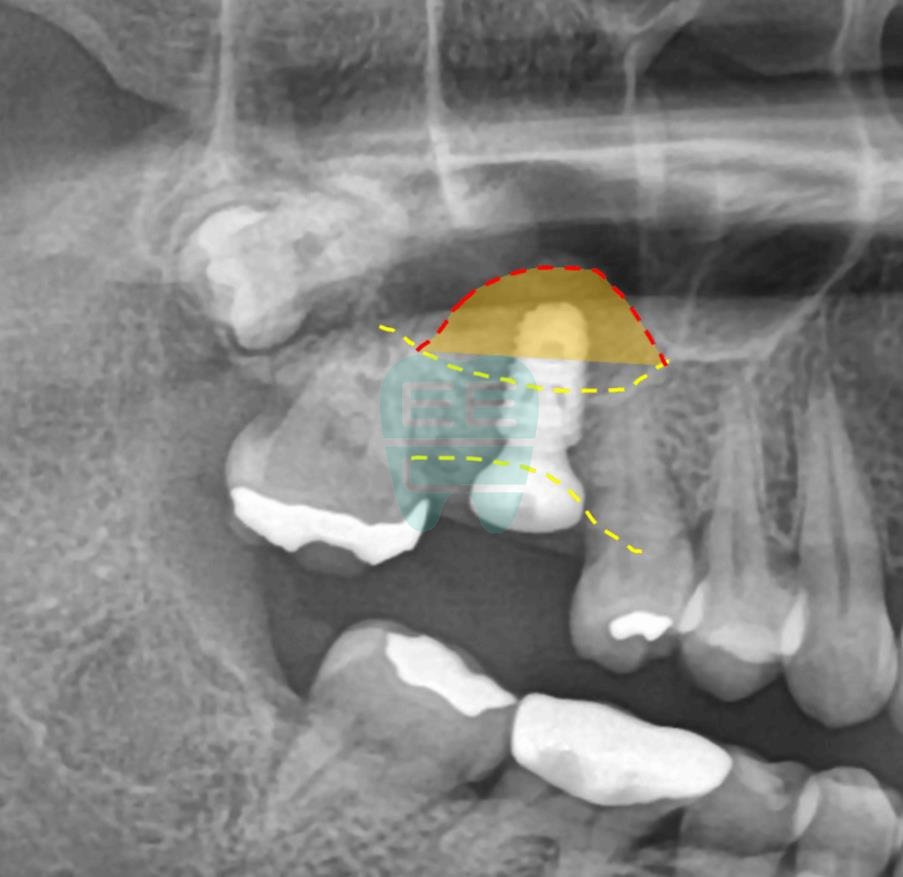

**Pre-operative Panoramic X-ray** — Confirming proximity to the maxillary sinus.

**Pre-operative CT Scan** — Insufficient bone height confirmed, sinus augmentation indicated.

**Post-operative Panoramic X-ray** — Implant securely positioned.

**Post-operative CT Scan** — Maxillary sinus membrane safely elevated.